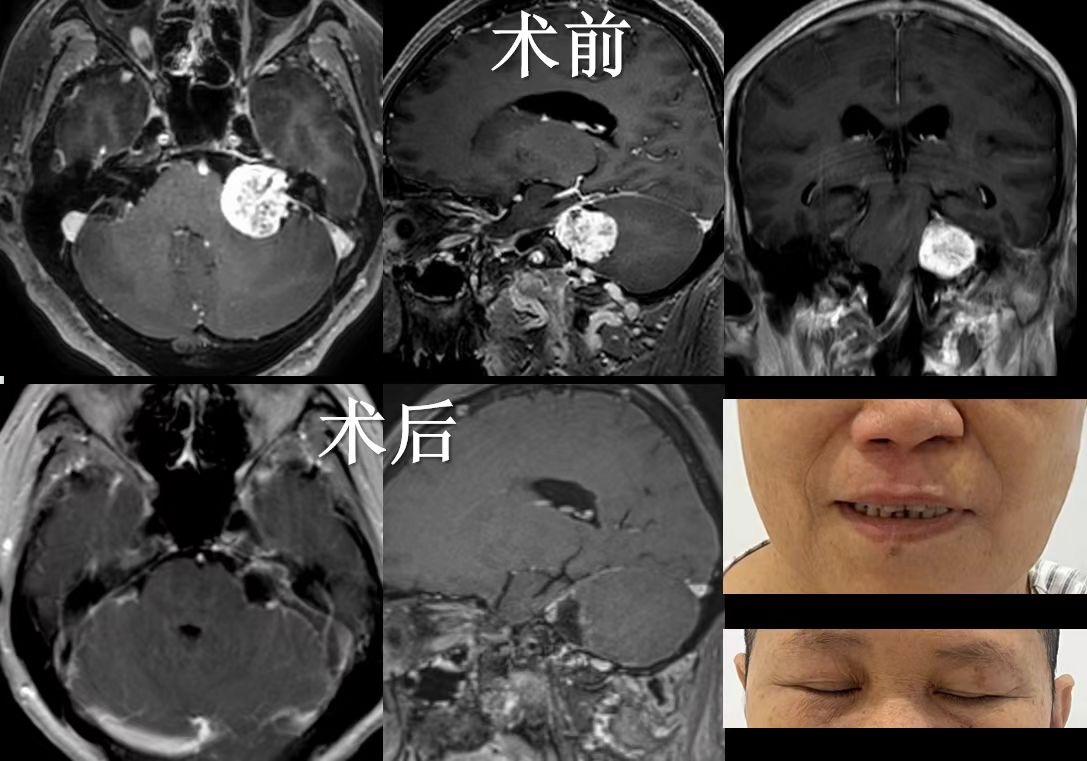

· MRI(磁共振成像): 是首选侦探,能清晰“拍”出肿瘤的位置、大小以及与周围神经、血管、脑干的亲密关系,如同绘制一份精准的“敌情地图”。

“精准拆除”(显微外科手术): 这是治疗的主要手段。目标是在保护面神经功能(避免面瘫)和尽可能保留残余听力的前提下,安全、彻底地移除肿瘤。手术如同在头发丝般纤细的神经丛林中拆弹,需要极高精度的“雕刻”技术。